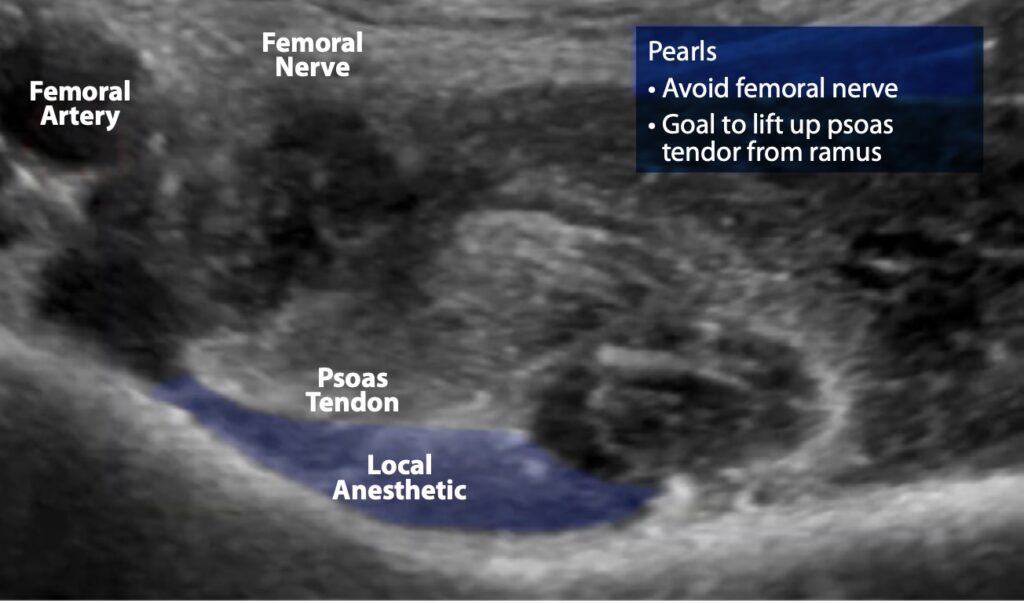

- Now administer 15-20 ml of dilute local anesthetic. Highly concentrated anesthetic is not needed for the PENG block because the nerves are small. No more than 20ml is required for successful block (larger volumes of anesthetic increases the spread of anesthetic and the consequent risk of lumbar plexus blockade). Correct administration of anesthetic will cause a lift of the iliopsoas tendon (figures 5,6,7).

Figure 8. Ultrasound image demonstrating anesthetic lifting the psoas tendon from the pubic ramus, indicating successful anesthetic deposition. The femoral nerve and artery have been avoided.

The most important complication to avoid is femoral nerve blockade, which occurs when excessive local anesthetic is administered.